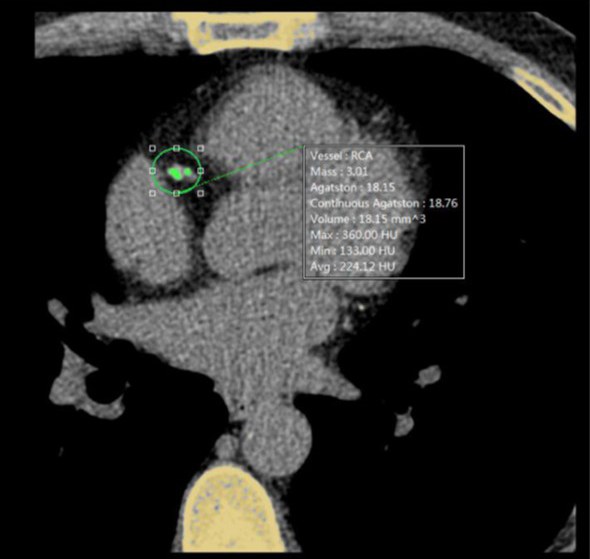

Coronary Calcium Scoring

Estimate the amount of calcium in the coronary arteries

• Agatston score

• Volume score

• ROI information calculation